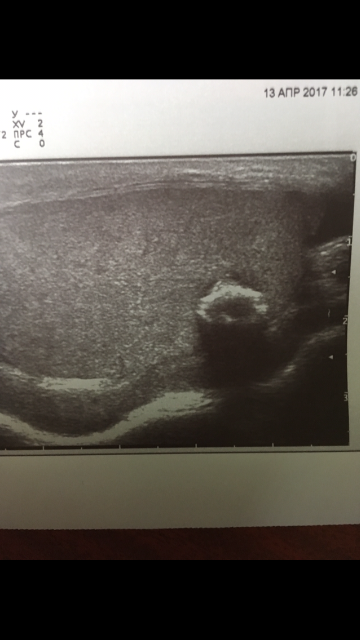

Образование в левом яичке

Выглядит обычным кальцификатом

Или кальцифицированная киста.

Возможно, но маловероятно, для кисты с кальцинированной стенкой больше характерен ровный контур и правильная форма

Согласен, это я покинул для диф.ряда.